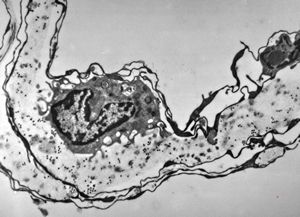

rabbit spinal cord trauma

rabbit spinal cord trauma